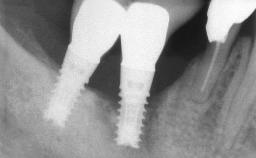

Peri-implant Carcinoma

Oral implants are highly successful and offer long-term benefits, especially in the rehabilitation of edentulous patients or patients with oral defects following ablative tumor surgery (Albrektsson and coworkers 1986), and also after radiation therapy (Schiegnitz and coworkers 2014). With the number of implants placed globally going into the millions, implant dentists have observed some rare adverse events. Although carcinogenesis around implants is an exceedingly rare phenomenon, we recently reported about 15 patients treated for carcinomas adjacent to implants at our clinical department over a period of fifteen years (Moergel and coworkers 2014). The following case represents a patient of this cohort; it discusses possible risk factors and makes suggestions for a recall schedule. A 70-year-old woman was referred to our outpatient department for evaluation of a rapidly growing macroscopic alteration of the mucosa in the left mandible.

# of Implants 4